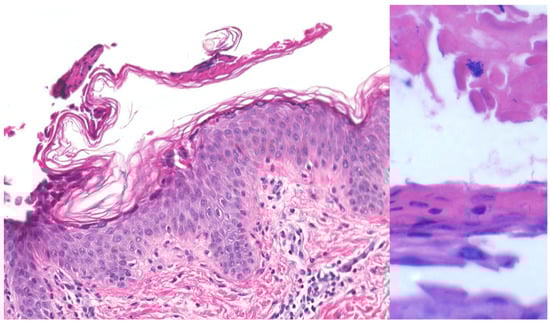

| Bullous impetigo [4,15] | Newborns and infants most commonly affected | Caused by S. aureus production of exfoliative toxins which cleave DSG1 resulting in acantholysis and bullae formation | Small vesicles that grow into tense bullae that rupture and leave behind a narrow rim of scale. The bullae appear in well-demarcated clusters at the initial site of infection. Systemic involvement is rare. Nikolsky sign is negative and culture of bullae or erosions is positive | Loss of cell adhesion in the superficial epidermis (granular layer) resulting in a subcorneal blister; mixed dermal inflammatory infiltrate, crusting, epidermal hyperplasia, and lesional cocci in clusters | Usually resolves within 3–6 weeks. However, high risk patients may develop SSSS due to dissemination of exfoliative toxin |

| Bullous impetigo [4,15] | Newborns and infants most commonly affected | Caused by exfoliative toxins produced by S. aureus, which cleave DSG1, resulting in acantholysis and bullae formation | Small vesicles that grow into tense bullae in well-demarcated clusters at the initial site of infection. Bullae rupture and leave behind a narrow rim of scale. Systemic involvement is rare. Nikolsky sign is negative, and culture of bullae or erosions is positive. | Loss of cell adhesion in the superficial epidermis (granular layer) resulting in a subcorneal blister; mixed dermal inflammatory infiltrate, crusting, epidermal hyperplasia, and lesional cocci in clusters. | Usually resolves within 3–6 weeks. However, high-risk patients may develop SSSS, due to dissemination of exfoliative toxin. |

| Pemphigus foliaceus [29] | Usually seen in adults 45–65 years old | Autoantibodies targeting desmoglein 1. Medications (captopril, penicillamine). Possible environmental triggers can cause Fogo Selvagem, a form of pemphigus foliaceus endemic to Brazil | Erythematous “puff pastry-like” crusted erosions often in seborrheic distribution, with a positive Nikolsky sign and no mucosal involvement | Subcorneal split in granular layer with acantholysis and scattered eosinophils +/− neutrophils. DIF shows intercellular IgG and C3 deposition primarily in the upper half of epidermis | Treatment with rituximab achieves complete remission in 90% of patients within two years |